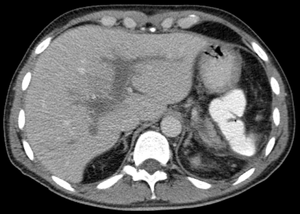

| Portal vein thrombosis seen with computed tomography. | |

The diagnosis of portal vein thrombosis is usually made by ultrasound, computed tomography with contrast or magnetic resonance imaging. D-dimer levels in the blood may be elevated as a result of fibrin degradation.